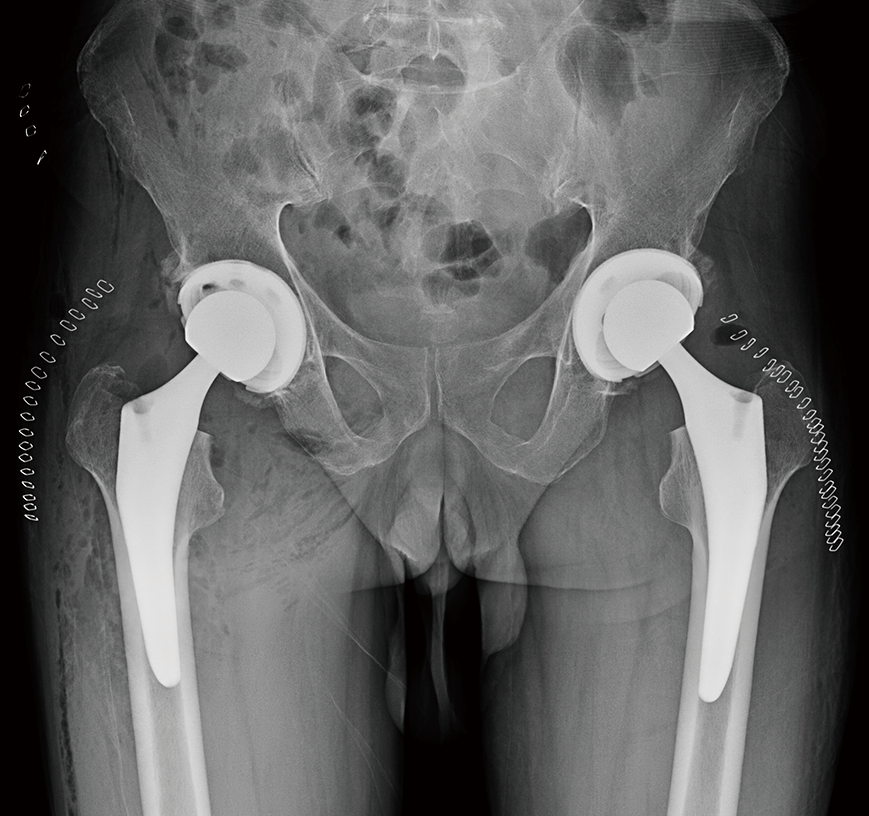

病例2:髋关节置换术后严重髋臼内陷, 使用3D打印垫块及组配柄完美重建